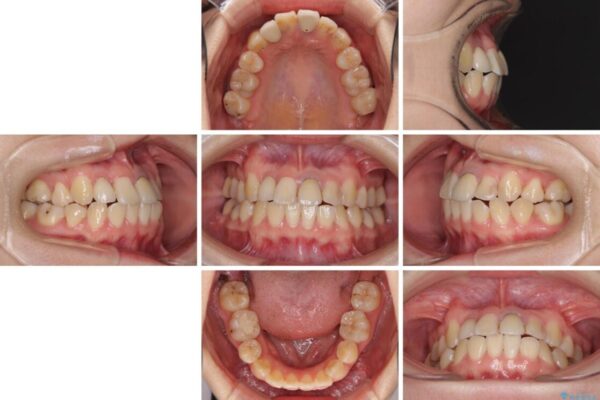

治療途中

• 虫歯治療ついでに歯並びの後戻りを改善 インビザラインによる矯正治療 治療途中画像